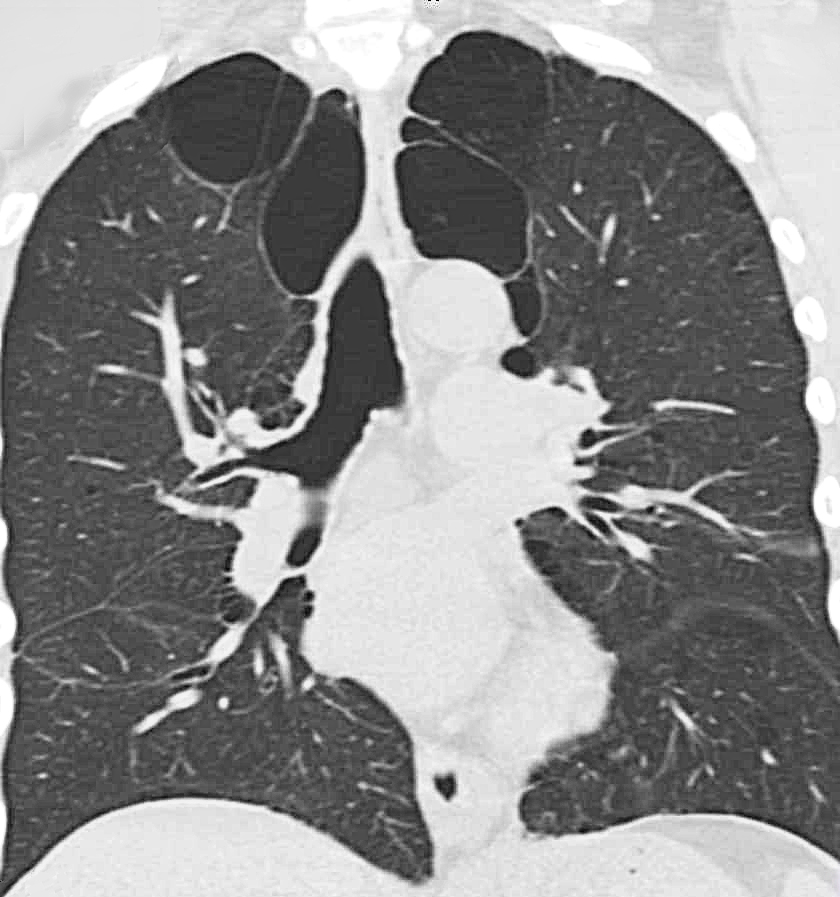

Emphysema is visible on ct scan

Emphysema (seen as darkened voids in the upper lungs) is clearly visible on a CT scan.

Imaging scans will tend to reveal hyper-inflated lungs with a depressed diaphragm. A CT scan may show a heterogeneous pattern of emphysema in the lungs, which is generally much worse in the upper lobes of the lung than in the lower lobes. This is usually confirmed with a lung perfusion scan.